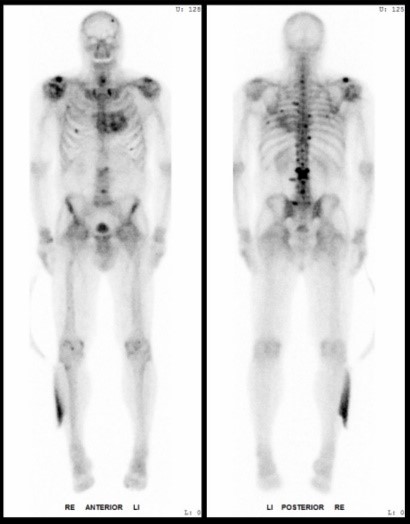

The offers range from basic scientific investigations, physical aspects of nuclear medicine, and radiological diagnostic as well as therapeutic diagnostic and therapeutic procedures to the supervision of interdisciplinary clinical studies.